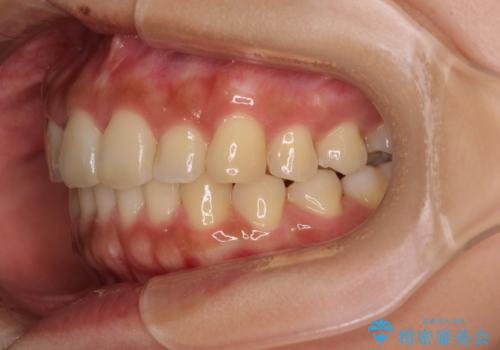

【モニター】歯列が狭くデコボコが気になる 急速拡大装置を用いたインビザライン矯正

- 奥歯の咬み合わせと治療を放置したまま奥歯を気にして来院された患者様です。

上顎骨の幅が下顎骨よりも小さいので、拡大装置により骨幅を広げて上下関係を改善し、その後インビザラインにて歯並びを整えることとしました。

矯正治療後には土台のままとなっている歯をセラミッククラウンにて補綴治療を行うこととしました。

上下の骨幅を改善したことで、スムーズに歯列矯正を行うことができました。

土台のまま放置されていた歯は土台の状態で咬み合っていましたが、急速拡大を行った際に咬み合わせが著しく挙上されたため、その際に土台を大きくすることで咬み合う歯との距離を確保しました。